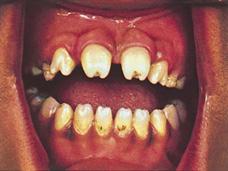

Es causada por la bacteria espiroqueta Treponema pallidum. La infección ocurre por la transmisión transplacentaria u ocasionalmente a través del contacto directo con una lesión infecciosa durante el nacimiento, la transmisión lo pueden hacer tanto las gestantes que tienen infección primaria o secundaria, así como las que están en fase latente, pero más riesgoso son las primeras; no se transmite por leche materna. Cuando el Treponema pallidum ingresa a la sangre del feto se disemina a casi todos los órganos dando clínica como resultado de la respuesta inflamatoria, los más afectados son hueso, hígado, páncreas, intestino, riñón y bazo. La presentación de estos pacientes puede ser como sífilis congénita temprana y tardía. La temprana se define por manifestaciones antes de los 2 años, aunque la mayoría son asintomáticos, si es que hace clínica resaltan la hepatomegalia, ictericia, secreción nasal (“resopla”), erupción maculopapular o vesicular (“pénfigo sifilítico”), linfadenopatía generalizada y anormalidades esqueléticas (periostitis (ENARM 2000), signo de Wegner [metáfisis en dientes de sierra], signo de Wimberger [destrucción ósea de la parte superior de la tibia]). La tardía se define por manifestaciones que inician después de los 2 años, entre ellos los rasgos faciales (protuberancia frontal, nariz en silla de montar, maxilar corto, mandíbula protuberante), oftalmológicas (queratitis, corioretinitis, glaucoma secundario, atrofia óptica), hipoacusia neurosensorial, orofaríngea (dientes de Hutchinson, molares de mora, paladar duro perforado), cutáneas (rhagades, gomas), del SNC (discapacidad intelectual, hidrocefalia, parálisis de pares craneales), esqueléticas (espinillas en sable, signo de Higoumnakis, articulaciones de Clutton).